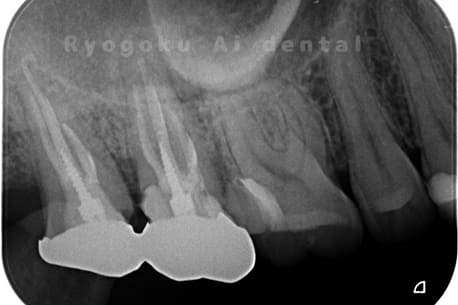

Case03

- 重度カリエス、慢性根尖性歯周炎

- 治療内容

- 自家歯牙移植

- 治療費用

- 220,000円

他院で右下の根の治療を行い、セラミックを被せる説明をされていたが、根の治療が終わらないため転院された患者さんです。隣の親知らずの抜歯の必要性と、根の治療を行なっている歯牙の予後が悪いため、移植治療を提案し、右下の親知らずの抜歯と同時に、右下の奥歯(7番)への移植治療を行いました。被せ物を行う必要もなく、順調に経過してます。

<リスク・副作用>

治療後、痛みや違和感、出血、腫れなどが出る事があります。喫煙者、糖尿病などの方の場合、歯が生着しない場合があります。